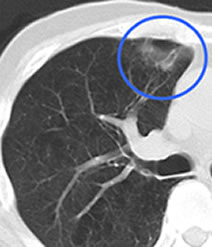

原発性肺がん

転移性肺がん(大腸からの転移)

原発性肺癌 ステージⅠ(肺結節のみ)

原発性肺癌 ステージⅢ(リンパ節転移)